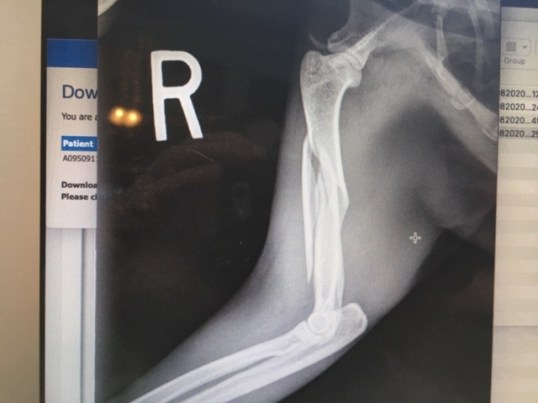

Baby Girl did indeed have a broken humorous. Likely from being hit by a car from one of the many stoopid humans who do those “dough nut” things on the street right where Miss Kandi feeds.

And here is her broken front leg.